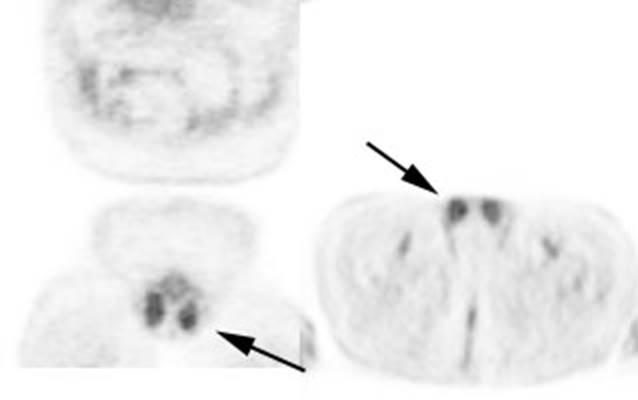

Figure 11 - Brown Fat: Prominent, symmetric

supraclavicular tracer uptake was seen in this patient without a corresponding

CT finding. Uptake in this area has been felt to be related to the presence of

"brown" fat.